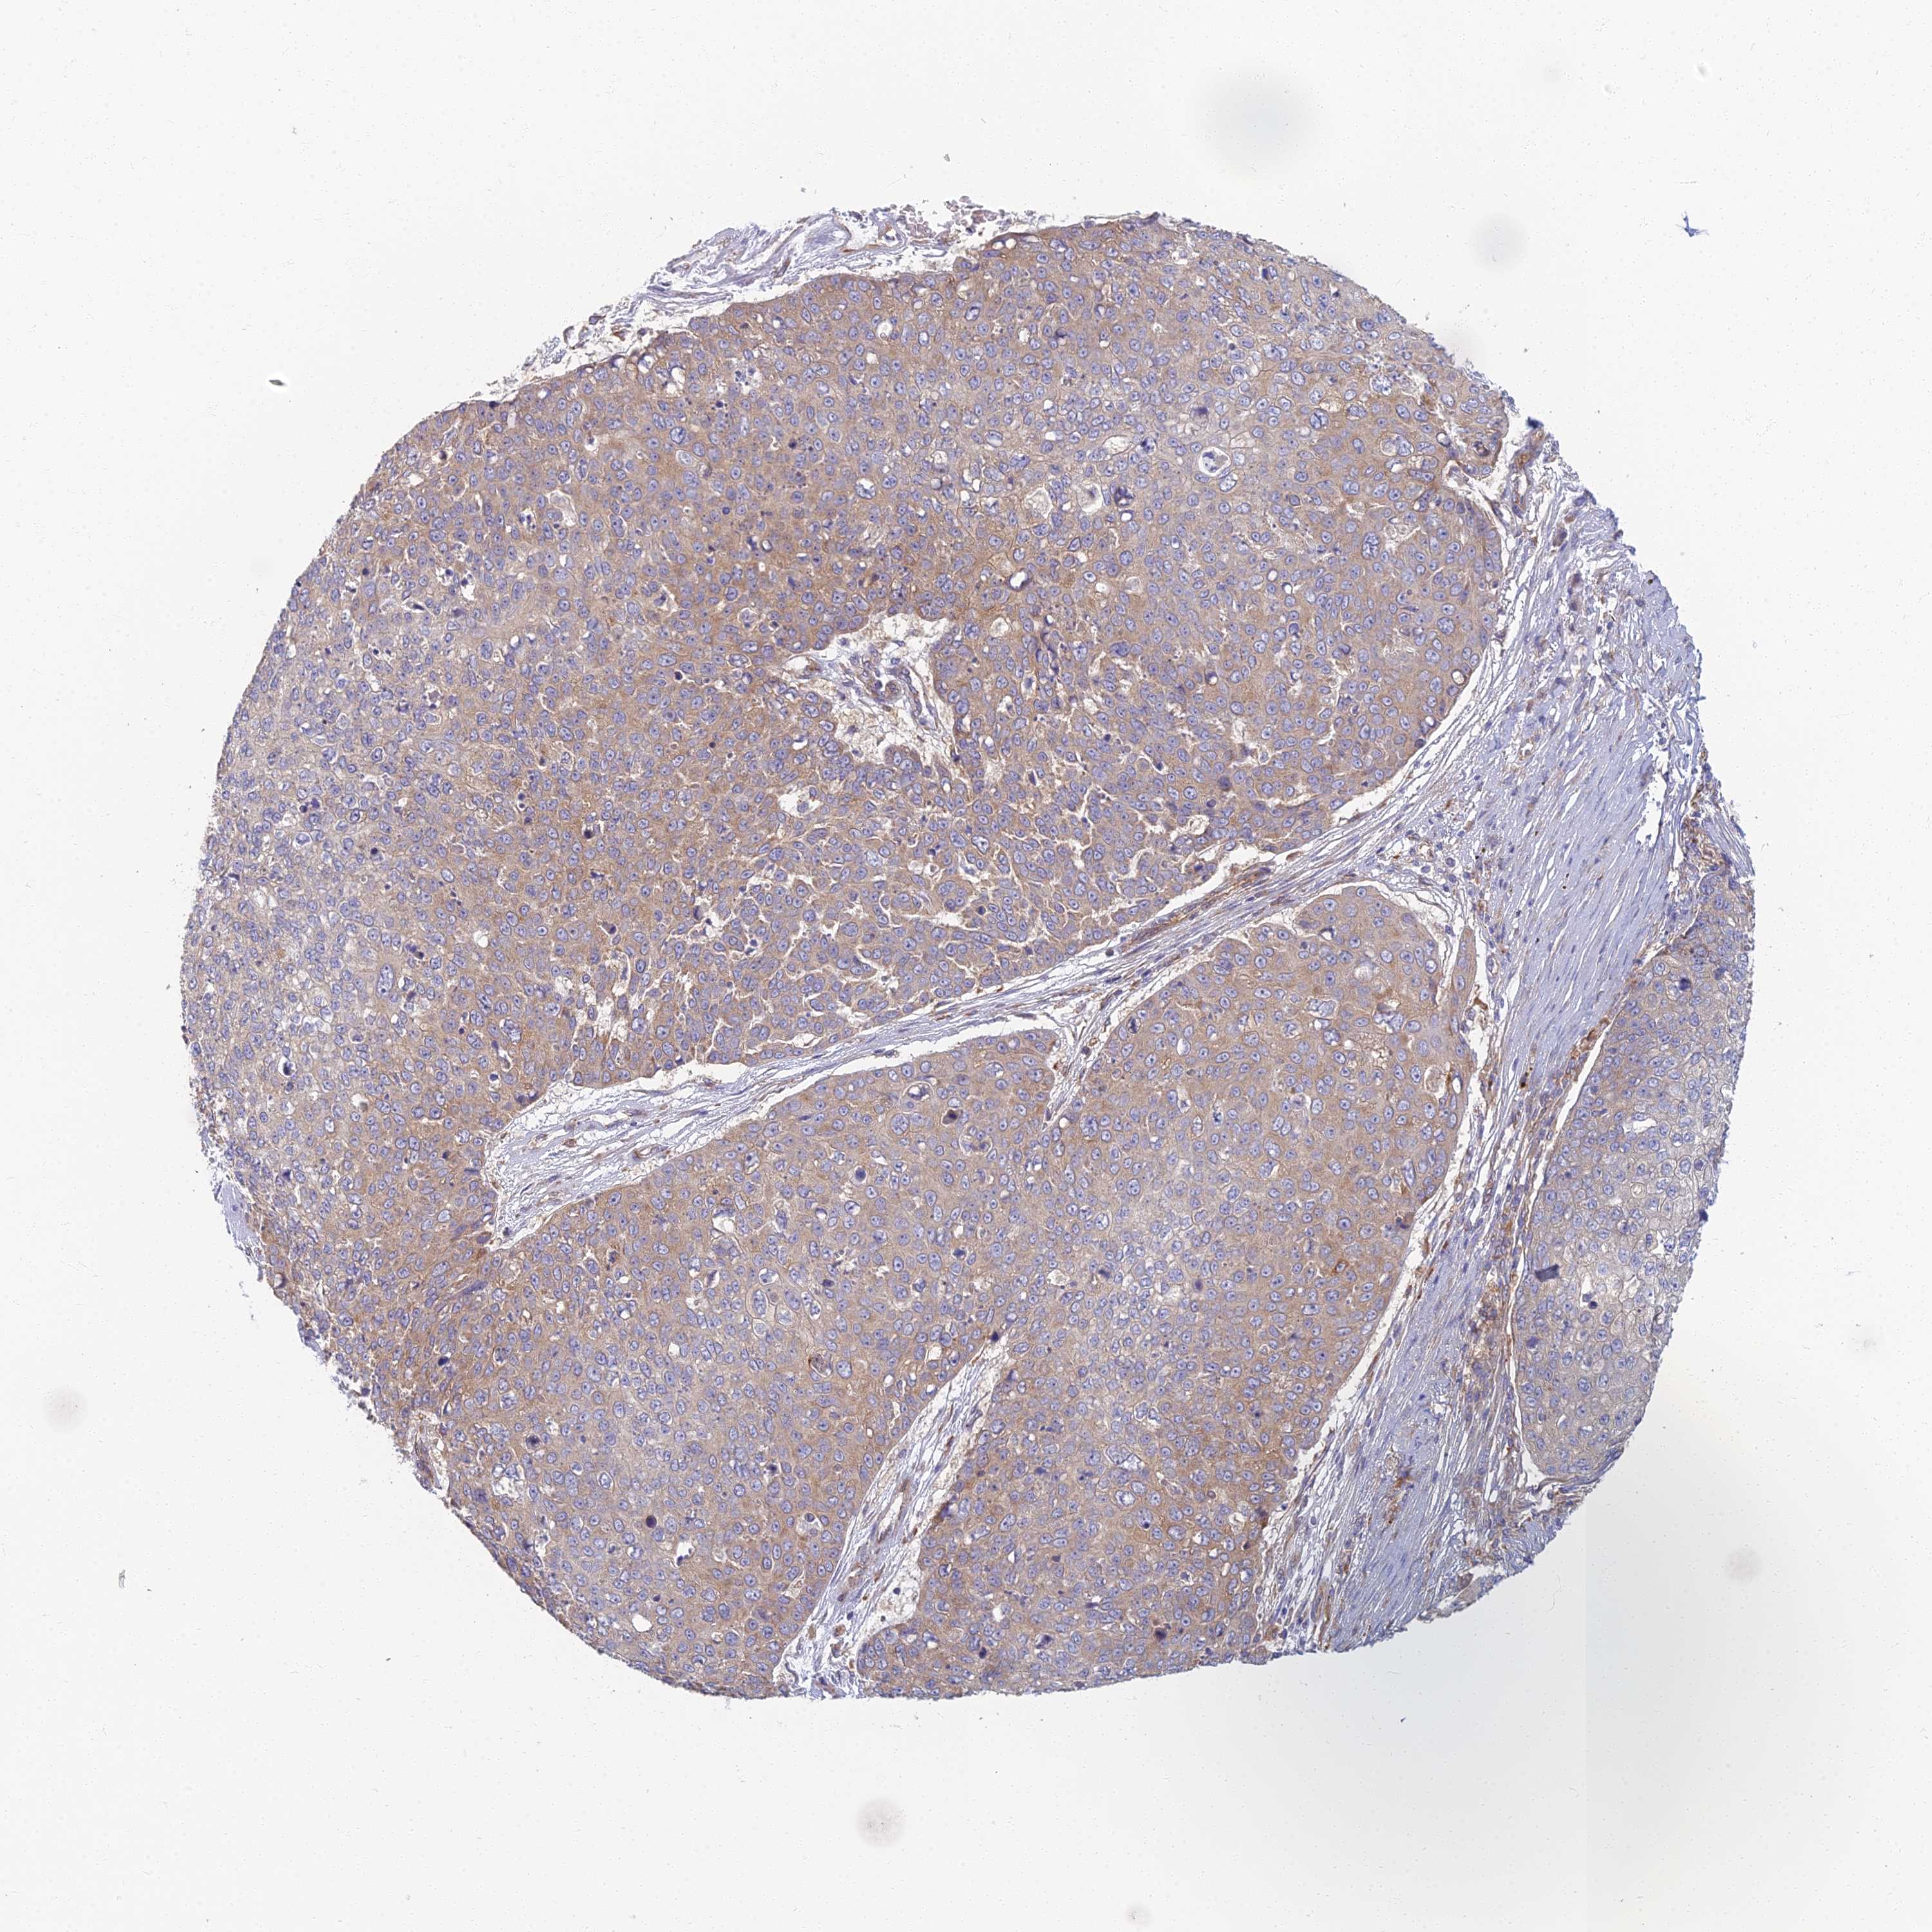

SKIN CANCER - Protein expressioni

A mouse-over function shows sample information and annotation data. Click on an image to view it in a full screen mode. Samples can be filtered based on level of antibody staining by selecting one or several of the following categories: high, medium, low and not detected. The assay and annotation is described here.

Each image is clickable and will lead to virtual microscopy that enables deeper exploration of all samples and also displays staining intensity scores, fraction scores and subcellular localization as well as patient and tissue information for each sample.

Antibody HPA044878

Staining

Low

Intensity

Weak

Quantity

<25%

Location

Cytoplasmic/membranous

Squamous cell carcinoma, NOS